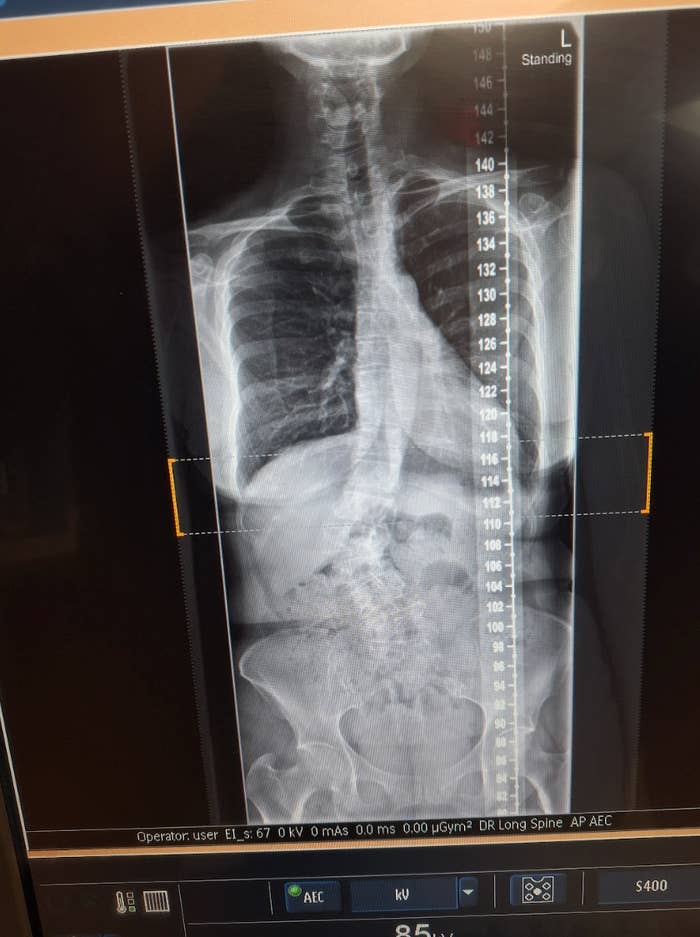

"I couldn't run from it any longer. The all-consuming pain impelled me to take a life-changing step." I stood before the screen gripping my lumbar, as the black-and-white X-rays stared back at me. I was 45 and I’d never gotten an X-ray — hardly been to a hospital except to be born and once for an extreme case of poison ivy. “That’s not me,” I protested, straightening my strained spine. I didn’t have anatomical terms for what I refused to see — the lower backbone bowed to the right in the shape of a capital C; the middle spine jogged to the left off-plumb; the shoulders and hips were cockeyed. “You got the X-rays mixed up.” “Sorry, it is,” the doctor traced the curve with his finger. “Bordering on severe scoliosis.” “But I just ran a 10-mile road race...” I winced, as fireworks exploded in my back, hips and legs. “Placed fourth in my age group, fastest time...” “You telling me you never knew?” He frowned. “The condition manifests in childhood.” Tears glossed my eyes, my fit middle-aged body crumpling in on itself, as a tiny seed of anger sprouted from a dark crevice. Where were my parents? In a flash, I was back to 1976 and my family’s pristine split-level house — white painted brick, black shutters, lemon-yellow door. Around that time, when kids got checked in gym class for scoliosis with a simple forward bend test, our upwardly mobile nuclear family was melting down. “You need to quit running,” said the doctor as he pressed his finger pads into my inflamed hump. An X-ray of the author's spine taken in 2023. During the fall of seventh grade, as I entered junior high, my father had lost another Pentagon contract and my mother’s dizzy spells kept her holed up in the blue bedroom. As the determined eldest child, I set my alarm for the crack of dawn and tiptoed out before my father awoke. When I joined the huddle of misfits on the blacktop — puffs of breath in the shivery morning air — I felt a small sense of victory. I’d escaped Dad’s inevitable wrath — the vindictive unpredictability of what I would much later discover was manic depression. Undiagnosed, he self-medicated with gin. Heart pounding, lungs panting, by the time we completed our first loop, thoughts of home had receded and, for a miraculous moment, it was just my body moving in rhythm with the pack. “Stop running, and see me back in a month.” The doctor handed me a prescription and walked out. Within weeks, I was back on the running trail, pushing through the pain. That doctor didn’t know what he was talking about. I’m 57 and running down a dirt road in Vermont — out for the daily endorphin fix. The scent of cow manure wafting in the breeze, arms and legs swinging in pendular rhythm, I was suddenly stopped in my tracks. My body was engulfed in flames of pain and I couldn’t take another step. I doubled over, sweat pouring off my head and my heart racing with panic. That time, I landed in the emergency room. The attending nurse took my vitals. “Pain level?” she asked, glancing up from her iPad. I shut my eyes, body screaming. The pain — stabbing, burning, shooting through my back, into my hips and down my prickly numbed-out legs — was exponentially worse than anything I’d ever felt. And it was everywhere. “Seven... eight? Nine.” My voice sounded guttural. My secret deformity was back — it had not disappeared. Perhaps it had worsened. And why not, after a decade defying doctor’s orders? “See, here?” The spine surgeon pointed to the new set of X-rays. “Serious lumbar curve of 45 degrees, apex here at L4, then a 20-degree rotation at T2 and T3. That’s where you get your disk compression and nerve impingement causing neuropathy in the legs.” “Neuropathy,” I murmured in a cortisol-infused daze. It was like seeing the snaking horror inside me for the very first time. “I’m sorry to have to tell you: You’re a candidate for surgery. The sooner the better — to prevent the spine from sinking further with gravity and time and impinging on vital organs.” “I won’t lie. It’s a big surgery. Six-to-12-month recovery. It’s easier when you’re younger. Late 50s? Lots of good years left.” Gripping the exam table, I caught sight of a spinal model adorned with bolts and rods; the gleaming steel sent a shiver straight up my contorted spine. “Will it stop the pain?” I bit my lips together, trapping sobs in my chest. “I’ve never... I don’t know who...” Who would take care of me? Parentless, partnerless, childless, petless — over the years, I’d successfully escaped any and all confines. Now this surgeon wanted to immobilize me from the inside — in a steel cage. He extended his hand to help me off the exam table. I didn’t want to let go. I wanted a savior so badly to make me all better — a magician to make this nightmare disappear. The author at Georgetown Hospital in 2024. The steroids the doctor prescribed were just a mask. When they wore off, weeks later, my broken body was back. I couldn’t walk five steps without squatting to catch my breath; couldn’t carry a thing — backpack, bag of groceries, tiny purse, a feather. I could barely stand at the vanity for long enough to brush my teeth. Through life’s roller-coaster ups and downs, my body had been one reliable constant. Cycling centuries, winning triathlons, running day in and out to keep my unruly chemicals in some kind of haphazard balance. Now I couldn’t even sit! Not a single seat in my house was tolerable. Sitting at my desk to get my work done? Impossible. Confined to my bed to avoid the pain, I felt myself sink. Storm clouds of suicidal ideation hung over me. Desperate thoughts — well, it’s been a good life and maybe my time is up — that induced a hot-flash of terror which, thankfully, thrust me out of bed onto my yoga mat. Stretched out in child’s pose, I exhaled a sigh as tears gushed. As a kid, and the top runner on my team, Coach said I made it look easy; but he’d been wrong. I didn’t love running — it hurt. Still, I went back day after day, year after year, because my body knew something I did not: the physical pain beat the emotional pain any day. Little could I know the two were inextricably entwined. My body-mind was screaming at me to wake up and do something. I couldn’t run from it any longer. The all-consuming pain impelled me to take a life-changing step. Two weeks later, for the first in my life, at 57 going on 58, I lay on a physical therapist’s table. “Start here at the sacrum,” said Dr. Jen, kneading her fingers into the rigid triangle of bone at the base of my spine. My eyes welled, less from outright pain and more from relief — the tenderness of being touched in that flawed, fragile place I didn’t want to acknowledge. All the MDs I’d seen never touched — just analyzed, diagnosed, prognosed, prescribed. As she pressed her palm against my hump, a well of sadness rose inside my cavity. Tears slid down my cheeks and out the massage table’s face hole. “Can’t you see it protruding? Not sure why ... how they never … caught this.” My diaphragm contracted. Breath held in my chest. I was back, again, on the parental neglect riff. Dr. Jen exhaled audibly. “So many ways parents go wrong.” She paused, spreading her hands across my throbbing scapula. I’d awoken that morning with new pain — a knife stabbing the meat between my shoulder-blades — body rebelling against me. “But the way I see it, they did you a favor. If they’d elected surgery — pretty crude back in the ’70s — you’d be up for re-surgery about now ... if that first surgery even took in the first place. Other scenario: the dreaded brace. Success rate less than 3%, because no kid can withstand being encased 23 hours a day.” I nodded, certain I could not have, as snapshot images appeared behind my eyelids: Dad teaching me to throw a perfect spiral, navigate a two-wheeler, and swing a wicked backhand. The author in bat pose (hanging baddha konasana) in 2024. “Either way, you’d have lost those early athletic years — runner, gymnast, tennis player. Who knows about all the cool things you’ve done as an adult — triathlons, bicycle tours. And didn’t you say you were a dancer?” “Salsa, swing, zydeco...” Quiet tears streamed. “Amazing.” Her hands gripped my shoulders. “You’re fit. You’ve got fortitude, Anne. You can do this.” “Do what?” Eyes closed, I listened for the answer I already knew in my wise old bones. My father had done some good, loving things — he’d seen my athletic potential and encouraged me. But he disappeared into an illness he refused to see, and he never came back. “I can’t let what happened to him happen to me. I’ll do anything.” I pushed up off the table, heart thumping, and wiped the snot from my face. Glancing out the window at the maple in fiery fall majesty, I felt the vise grip on my lumbar ever so slightly loosen as I stretched out on the floor to learn my exercises. One year later, I stood before new X-rays. “No change,” the surgeon scratched his chin. Tears glossed my eyes. This was good news for my blessed, degenerative spine I’d come to call “Caroline.” “What are you doing?” the doctor asked as he cocked his head. “Everything,” I said, grinning, stance strong. I’d hiked mountains, swum rivers, practiced yoga everywhere — forests, beaches and deserts. I’d begun to dance again. Dr. Jen had opened a door. Then my exploration took its own adventurous course. I attended shaman ceremonies in Santa Fe, past-life regressions in Sedona, yoga for scoliosis in Asheville, and sought Chinese medicine in Montana. Through specialized Schroth therapy, I was learning to stand and to breathe — basic bodily capacities — in whole new ways. Caroline had done her best with the structure given; it was up to me, now, to counter a lifetime of adaptive misalignment. Yet full recovery meant going deeper. Through somatic therapy, I was facing the neglect of the past and learning to release not just my parents, but me, from the blame and shame of our wounding history — and, with it, the tension held in my body over decades. This was a great weight off my shoulders — and off Caroline. The willful eldest in me, determined to make everything OK when it just wasn’t, could simply, with practice, with daily, moment-by-moment reminders, surrender. The author in warrior II pose (virabhadrasana II) in 2025. My spine was no straighter, but it also wasn’t more crooked, and it had not sunk into vital organs. The pain hadn’t vanished, but it wasn’t debilitating. Most days it mostly receded, hovering around 1, 2 or 3. When the pain did flare up, I knew how to calm the flames — rest or swim or soak in a tub instead of pretending the ailing away or buying into its inevitable worsening. I wasn’t cured. Curing is passive and temporary. Healing, on the other hand, is an active, ongoing process that involves not just body, but mind, heart and spirit. My healing continues. Now four years in, I see this as a lifelong journey, deepening the connection to myself, learning to nurture the child within — showering her with the loving care she always deserved. Despite my best efforts, there may still come a day when spinal fusion is necessary. By then, I trust my body-mind will be prepared to make that decision from a place of love, not fear, and transform a cure into healing. Anne Marina Pellicciotto (Marina), founder of SeeChange, is a mind-body coach, speaker and yoga instructor who guides individuals to live boldly and creatively. A three-time recipient of the D.C. Arts and Humanities fellowship for literature (FY24-26), she was nominated for a 2024 Pushcart Prize. Marina completed her debut memoir, “Strings Attached,” and is seeking representation. This essay is drawn from a work in progress, “Crooked Spine Chronicles: A Midlife Nomad Journey to Healing.” Learn more about her writing and healing at www.seechangeconsulting.com. This article originally appeared on HuffPost in February 2026.